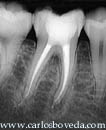

Primer Molar Inferior Derecho

El paciente es referido a nuestra consulta presentando una gran caries vestibular en el primer molar inferior derecho.

El paciente llega a nuestra consulta presentando una cavidad de caries extensa en vestibular del primer molar inferior derecho. El paciente refiere nunca haber sentido molestia alguna en este molar. El diente responde muy ligeramente a las pruebas de vitalidad pulpar.

Radiográficamente se aprecia una gran área radiolúcida coronal que invade el complejo dentino pulpar, así como dos pequeñas áreas radiolucidas localizadas en relación a los periapices de este molar.